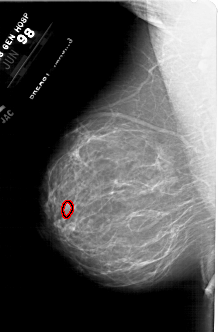

A_1787_1.LEFT_MLO

LEFT_MLO LINES 6301 PIXELS_PER_LINE 4126 BITS_PER_PIXEL 12 RESOLUTION 43.5 OVERLAY

FILE: A_1787_1.LEFT_MLO.OVERLAY

TOTAL_ABNORMALITIES 1

ABNORMALITY 1

LESION_TYPE MASS SHAPE LOBULATED MARGINS ILL_DEFINED

ASSESSMENT 4

SUBTLETY 1

PATHOLOGY BENIGN

TOTAL_OUTLINES 1

BOUNDARY